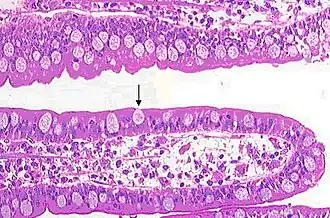

As células caliciformes são facilmente identificadas pelo seu núcleo basal e restante volume celular ocupado por grandes e redondos grânulos de muco. Na visualização pelo microscópio óptico convencional, geralmente o tecido é submetido ao preparo histológico de inclusão em xilol, o que faz o muco ser removido. Na coloração de rotina em HE (hematoxilina e eosina) a região dos grandes e redondos grânulos de muco é visto em coloração clara.

Célula caliciforme no íleo

Célula caliciforme no íleo -